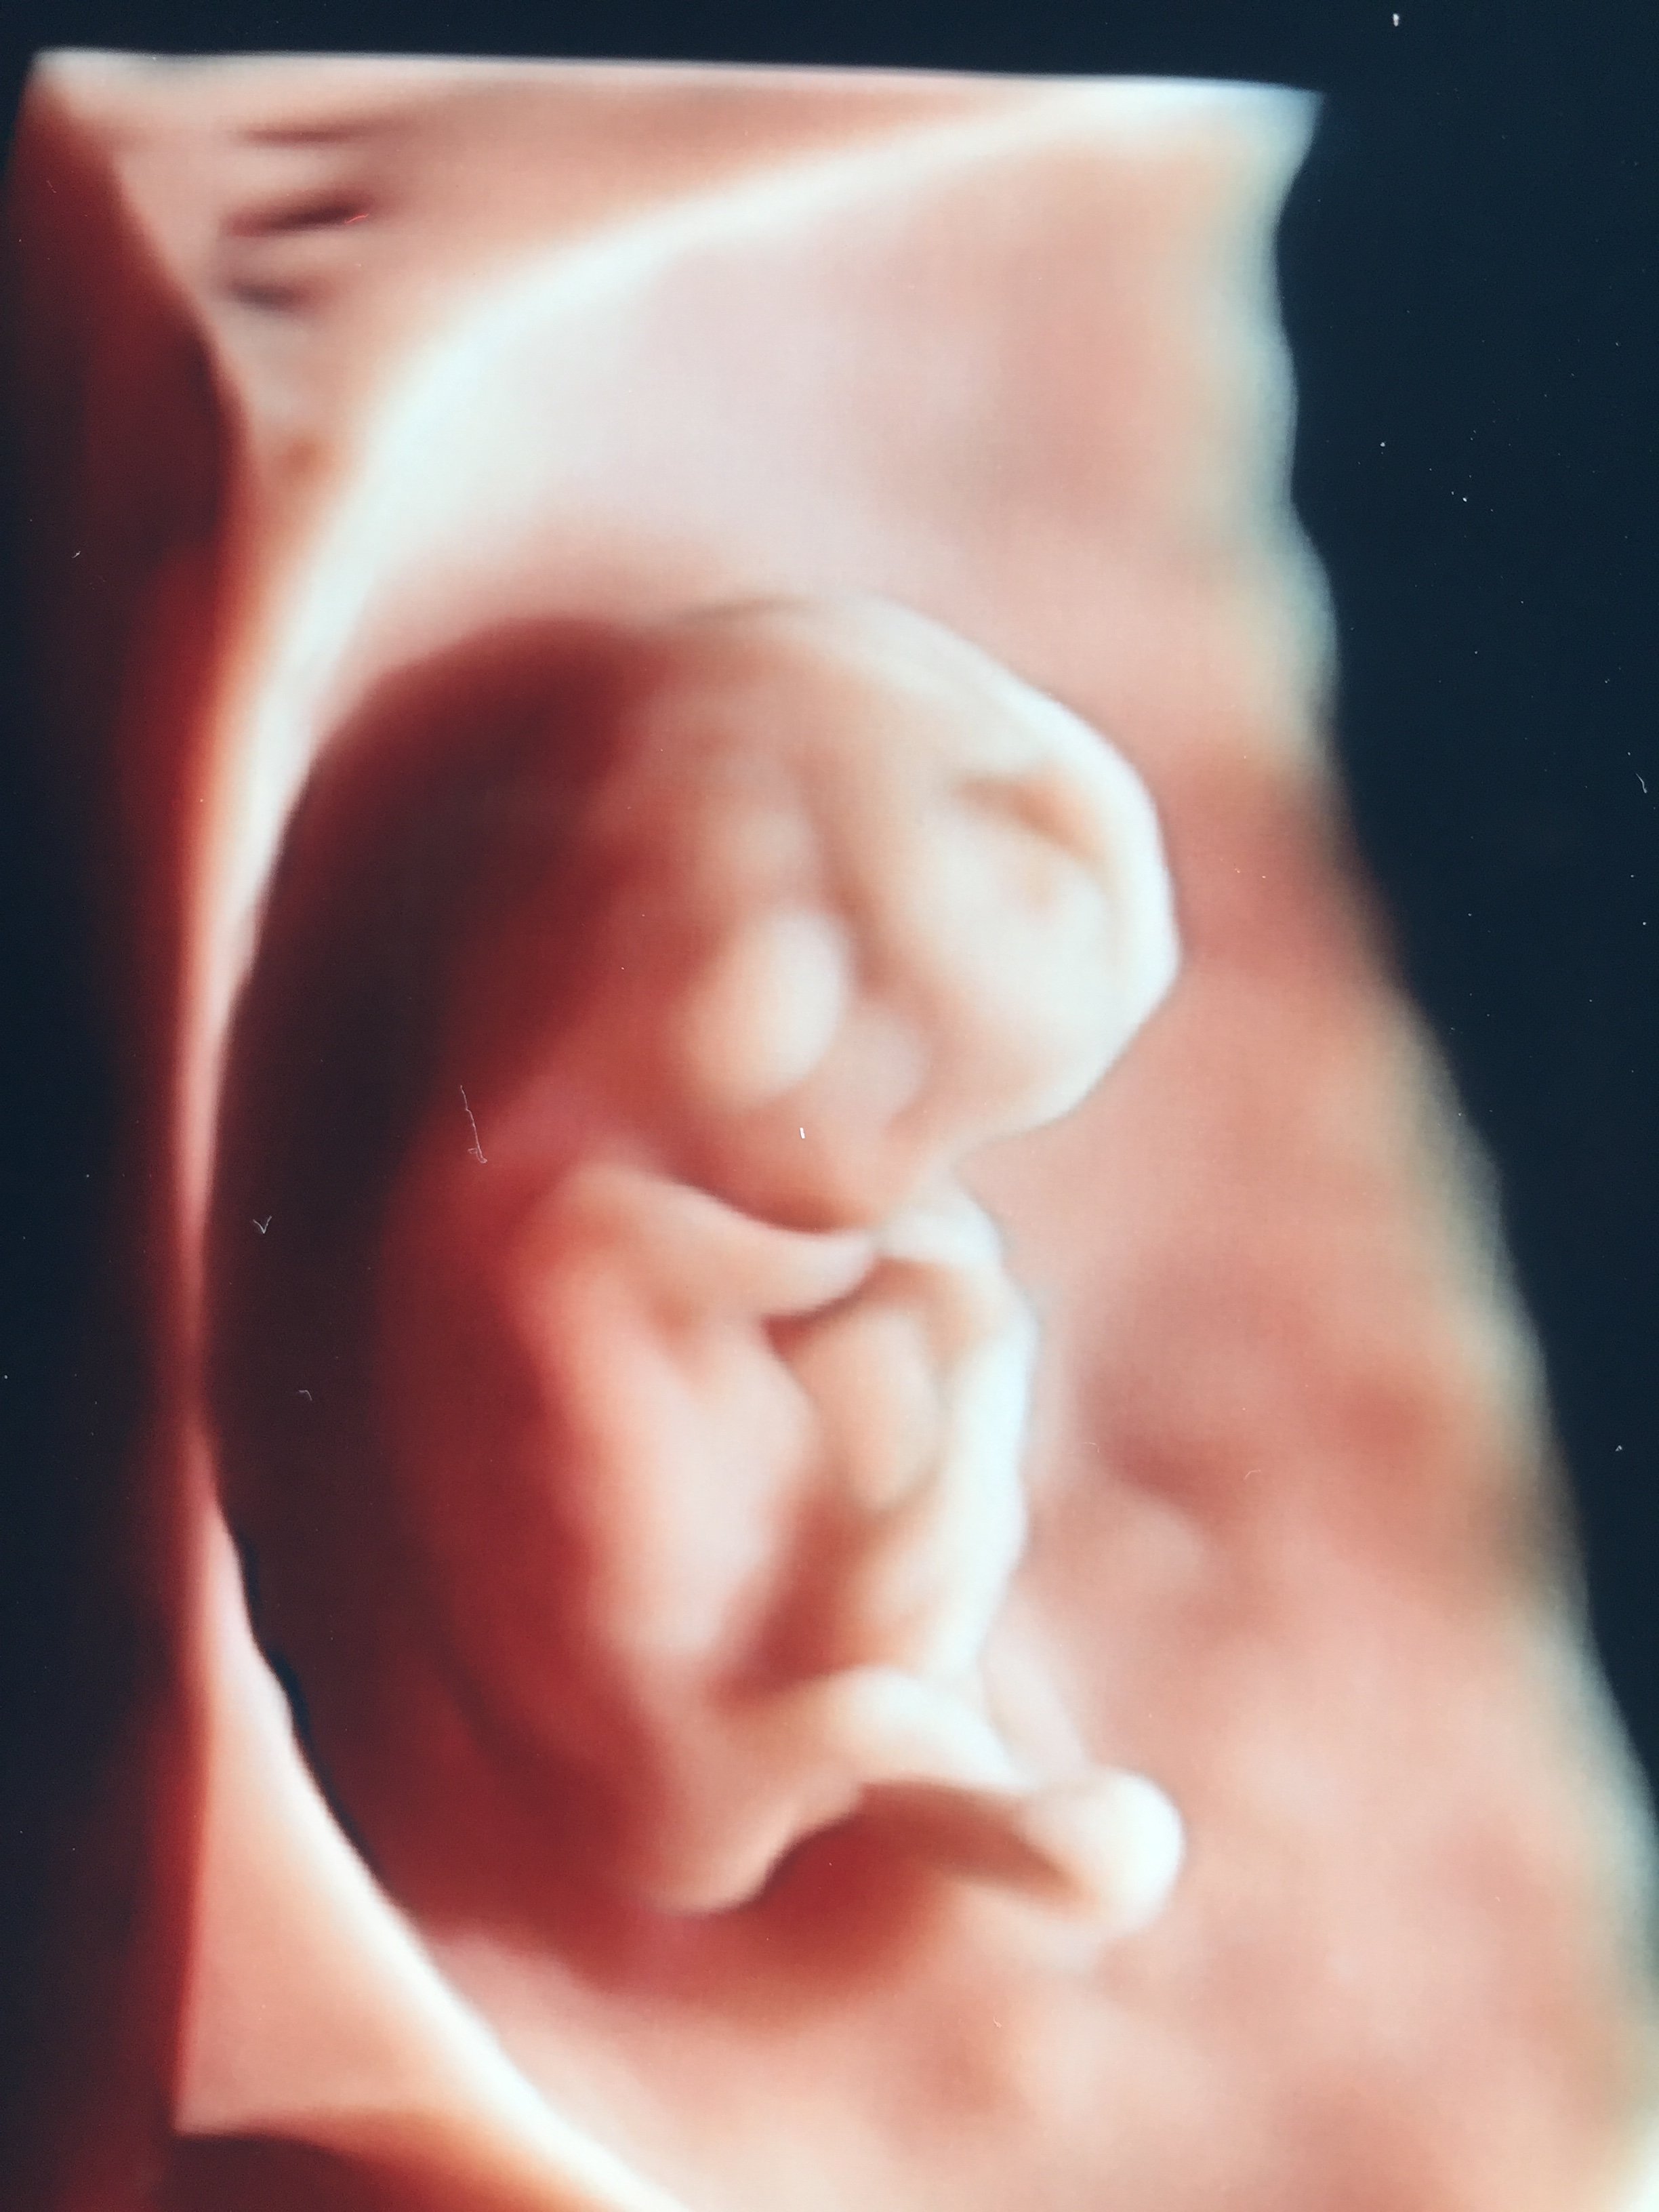

Wstawiam zdjęcie dzidziusia z ostatniej wizyty, mam nowa gin która ma super sprzęt

Zobacz załącznik 894434